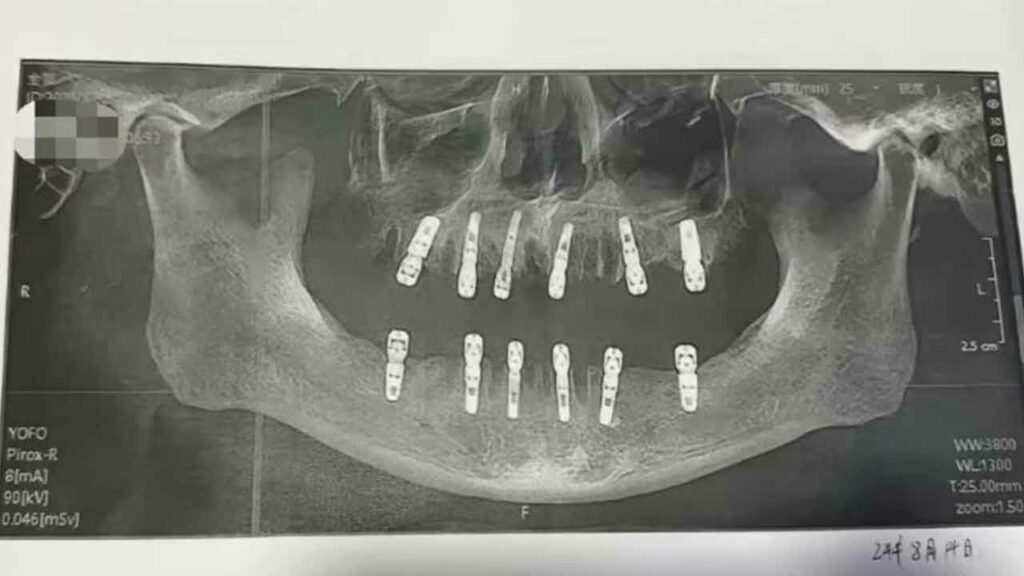

చైనా( China )కు చెందిన హువాంగ్ అనే వ్యక్తికి తీవ్రమైన దంతాల సమస్య రావడంతో.. స్థానికంగా ఎంతో ఫేమస్ ఉన్న డీవే డెంటల్ క్లినిక్( DeWay Dental Clinic )కు ఈ ఏడాది ఆగస్టు 14ఇవ తేదీన వెళ్లాడు. రోగి అనుమతితో డాక్టర్లు( Doctors ) ఒకేసారి 23 దంతాలు తొలగించారు. అదే రోజు.. కొత్తగా 12 దంతాలను చేర్చారు. ఈ సర్జరీ విజయవంతం కావడంతో.. హువాంగ్ను ఇంటికి పంపించేశారు డాక్టర్లు.

ఇక హువాంగ్ కోలుకుంటున్నాడనే సమయానికి అంటే సర్జరీ జరిగిన 13 రోజులకు గుండెపోటు( Heart Stroke )తో ప్రాణాలు విడిచాడు. ఈ సందర్భంగా ఆస్పత్రి యాజమాన్యం మీడియాతో మాట్లాడుతూ.. తమ దగ్గర సర్జరీ విజయవంతం అయిందని, హువాంగ్ మరణానికి గల కారణాలు తెలియాల్సి ఉంది. అయితే దవడల భాగంలో ఉండే దంతాలను తొలగించిన రోజే.. కొత్త దంతాలు ఇంప్లాంట్ చేయడం సరికాదన్నారు. ఎందుకంటే ఇది ఇతర సమస్యలకు దారి తీస్తుందని చెప్పారు. వయసు పైబడిన వారు సాధారణంగా 28 నుంచి 32 దంతాలను కలిగి ఉంటారు. అందులో 23 దంతాలను ఒకేసారి తొలగించడం సరికాదని పేర్కొన్నారు. అయితే రోగి హువాంగ్ అనుమతితోనే దంతాలను తొలగించామని స్పష్టం చేశారు.